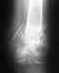

Спасибо большое за ответ, но, насколько я поняла, операция была рядовая, длилась час и 15 минут в обычной больнице, пластина и винт - как у многих при трехлодыжечном переломе с подвывихом, дальше - пластиковый гипс, ничего особенного,однако в сети нашла информацию, что применяют и ортезы жесткой иммобилизации, для каких же случаев они применяются? Их же для каких -то целей выпускают!К вам я обращаюсь, что знать еще одно мнение - это важно для меня.